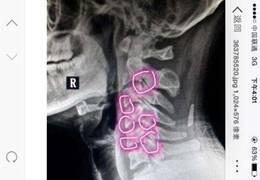

3、严重的颈椎退变

(1)颈椎失稳,牵拉、卡压神经

(2)颈椎增生、狭窄,卡压神经

(3)肌肉痉挛,卡压神经

(4)头、颈、肩部顽固性头痛,颈部活动明显受限

(5)颈椎脊神经后支射频治疗

颈椎及颈椎间盘的病变

4、颈椎病病因

(1)椎间盘退变,椎间隙狭窄

(2)关节囊、韧带松弛、脊柱稳定性下降

(3)骨赘形成,前纵和后纵韧带骨化

(4)脊髓、神经和血管受损

(5)钩椎关节附近骨质增生,可压迫椎动脉血流减少,可晕厥